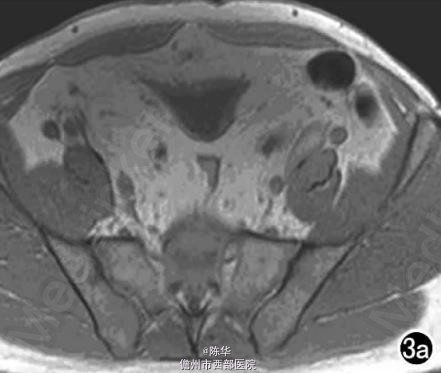

腹部B超示双肾增大,双肾慢性肾病声像;双肾中度积液伴双输尿管上段扩张。 IVPshi双侧输尿管中或下段梗阻。 膀胱造影:经尿道置管后,注射对比剂充盈膀胱,膀胱下半部先充盈,继续灌注对比剂后见膀胱完全显影,膀胱形态异常,呈“倒葫芦状”(图1)。 CT增强扫描行延迟期 MPR重组,见双侧肾盂、肾盏扩张积液;双侧输尿管纡曲、扩张,下端呈鸟嘴样变窄;膀胱变形、体积减小(图2); MRI平扫示双侧肾盂、肾盏扩张积液,双侧输尿管扩张并下端鸟嘴样变窄,盆腔内多量脂肪沉积,分布于膀胱、直肠周围,T1WI、T2WI呈明显高信号,T2WI抑脂像呈稍高信号,膀胱受压变形、体积减小(图3a~c); MRU示双侧肾盂肾盏扩张、积液,双侧输尿管显著纡曲、扩张,下端鸟嘴样变窄,管壁光整,膀胱变形、体积较小、位置抬高(图3d)。